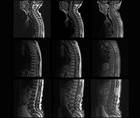

CADASIL Misdiagnosed as Multiple Sclerosis